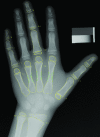

Purpose The Radiological Society of North America (RSNA) Pediatric Bone Age Machine Learning Challenge was created to show an application of machine learning (ML) and artificial intelligence (AI) in medical imaging, promote collaboration to catalyze AI model creation, and identify innovators in medical imaging. Materials and Methods The goal of this challenge was to solicit individuals and teams to create an algorithm or model using ML techniques that would accurately determine skeletal age in a curated data set of pediatric hand radiographs. The primary evaluation measure was the mean absolute distance (MAD) in months, which was calculated as the mean of the absolute values of the difference between the model estimates and those of the reference standard, bone age. Results A data set consisting of 14 236 hand radiographs (12 611 training set, 1425 validation set, 200 test set) was made available to registered challenge participants. A total of 260 individuals or teams registered on the Challenge website. A total of 105 submissions were uploaded from 48 unique users during the training, validation, and test phases. Almost all methods used deep neural network techniques based on one or more convolutional neural networks (CNNs). The best five results based on MAD were 4.2, 4.4, 4.4, 4.5, and 4.5 months, respectively. Conclusion The RSNA Pediatric Bone Age Machine Learning Challenge showed how a coordinated approach to solving a medical imaging problem can be successfully conducted. Future ML challenges will catalyze collaboration and development of ML tools and methods that can potentially improve diagnostic accuracy and patient care. © RSNA, 2018 Online supplemental material is available for this article. See also the editorial by Siegel in this issue.